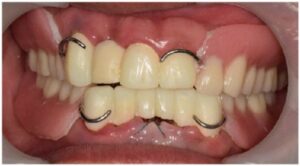

의식하진정법을 동반하여

발치 후 위아래 양측 어금니 부위에

정확한 방향으로

안정적인 식립을 도와드렸습니다.

식립해 둔 임플란트가

단단히 결합되기를 기다리는 동안

위아래 앞니 브릿지 보철물 수복을 위한

치아 다듬기를 진행하였으며,

발치 부위의 잇몸이 아물기 전까지

임시치아를 사용하실 수 있도록

도와드렸습니다.